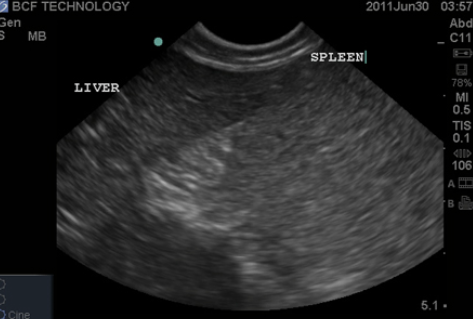

Echogenicity of common organs

spleen is hyperechoic to liver

Spleen

elliptical, flat, with smooth contours

more echogenic than liver